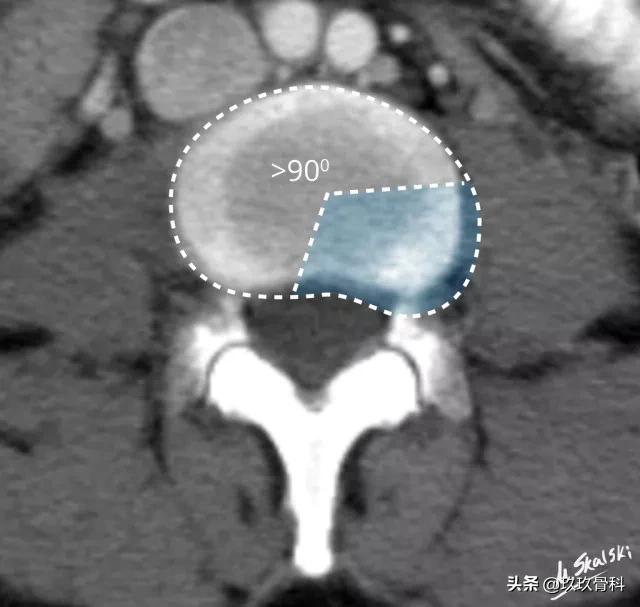

图 3 椎间盘膨出的影像学定义为突出部分>椎间盘边缘的25%,或者突出的两边与髓核的中心的夹角>90°